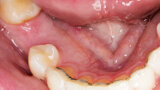

Řízená implantologie za použití řešení Planmeca all-in-one